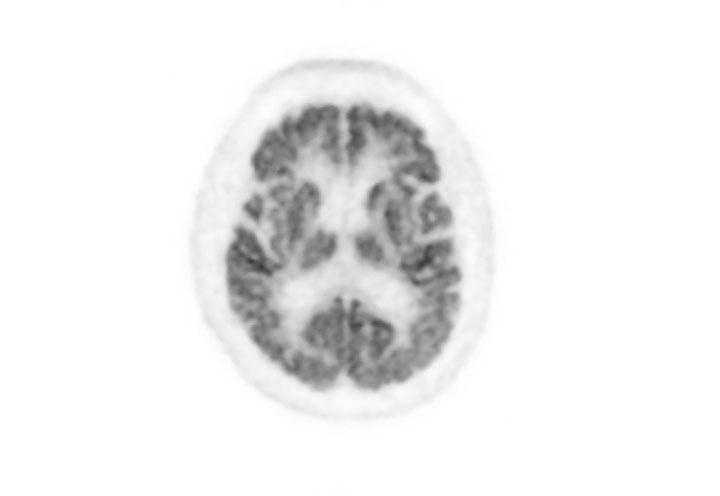

Head / Case2 : FDG

Courtesy : Kindai University Hospital

- Imaging protocol

- Injected dose: 3.29 MBq/kg, 18F-FDG

- Uptake time: 38 minutes

- Scan time: 30 minutes